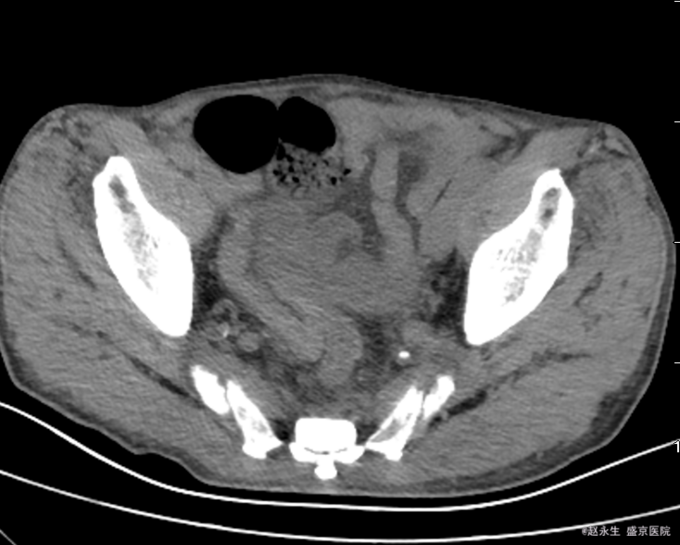

查体::腹膨隆,未见肠型及蠕动波,未触及明确包块,全腹压痛,反跳痛及肌紧张,肝区叩痛阴性,肾区叩痛阴性,Murphy征阴性。肝浊音界未见减少,移动性浊音阳性,未闻及肠鸣音。 辅助检查:急诊查腹部CT平扫提示:乙状结肠扭转,肠梗阻.盆腔多发渗出,积液.

诊断:乙状结肠扭转 治疗:急诊全麻下行剖腹探查,乙状结肠部分切除,远端闭锁,近端造瘘术。术中探查见左侧腹腔巨大肠畔,张力较高,肠壁因扩张导致菲薄,肠壁暗红有点状缺血坏死征象,有一处肠壁浆膜裂开,有少许出血,扩张肠管周围及盆腹腔有草黄色渗出,吸净渗出,轻轻将扩张肠管娩出腹壁外,证实扩张的肠管为乙状结肠,仔细检查,见乙状结肠系膜较长,肠管顺时针扭转360°形成完全性肠梗阻,横结肠,降结肠扩张,有较多内容物,未触及肿瘤,胃空虚。